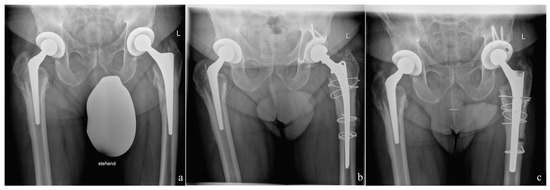

2. Material and Methods

2.3. Surgical Procedure